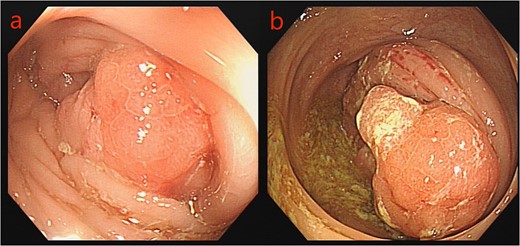

A 75-year-old male patient was admitted to the Department of Hematology due to small B-cell lymphoma. The patient had been experiencing incomplete intestinal obstruction for nearly 1 year and had been self-medicating with diarrhea-inducing medication obtained outside the hospital. During hospitalization, the patient exhibited a marked decline in appetite, accompanied by cessation of bowel movements, nausea, and vomiting. The patient weighed 85 kg, stood at 1.68 m tall, and had a body mass index of 30.12 kg/m2. He had no history of smoking, alcohol consumption, or surgery. Physical examination: the patient’s body temperature, heart rate, and blood pressure were normal, with abdominal distension, scattered abdominal tenderness without obvious rebound pain, and drumming sound on abdominal percussion. Laboratory tests: platelets, tumor markers CEA, the rest showed no abnormality. Chest computed tomography (CT) showed a few infection foci in the lungs, with no metastatic foci observed. Enhanced CT scanning of the abdomen revealed tumors in the sigmoid and ascending colon, with significant thickening observed in the proximal sigmoid colon tumor (Fig. 1). Colonoscopy revealed complete obstruction of the sigmoid colon (Fig. 2).

The patient was referred to the Department of Gastrointestinal Surgery. After electronic colonoscopy showed a neoplasm located 65 cm from the anus, biopsy confirmed it as adenocarcinoma. Placement of a tumor stent was unsuccessful due to complete bowel obstruction. Given the patient’s comorbid small B-cell lymphoma and our inability to ascertain the nature of the ascending colon tumor, emergency surgery was performed, specifically, a transverse colostomy was executed.

Colonoscopy images: a: sigmoid tumor; b: ascending colon tumor.